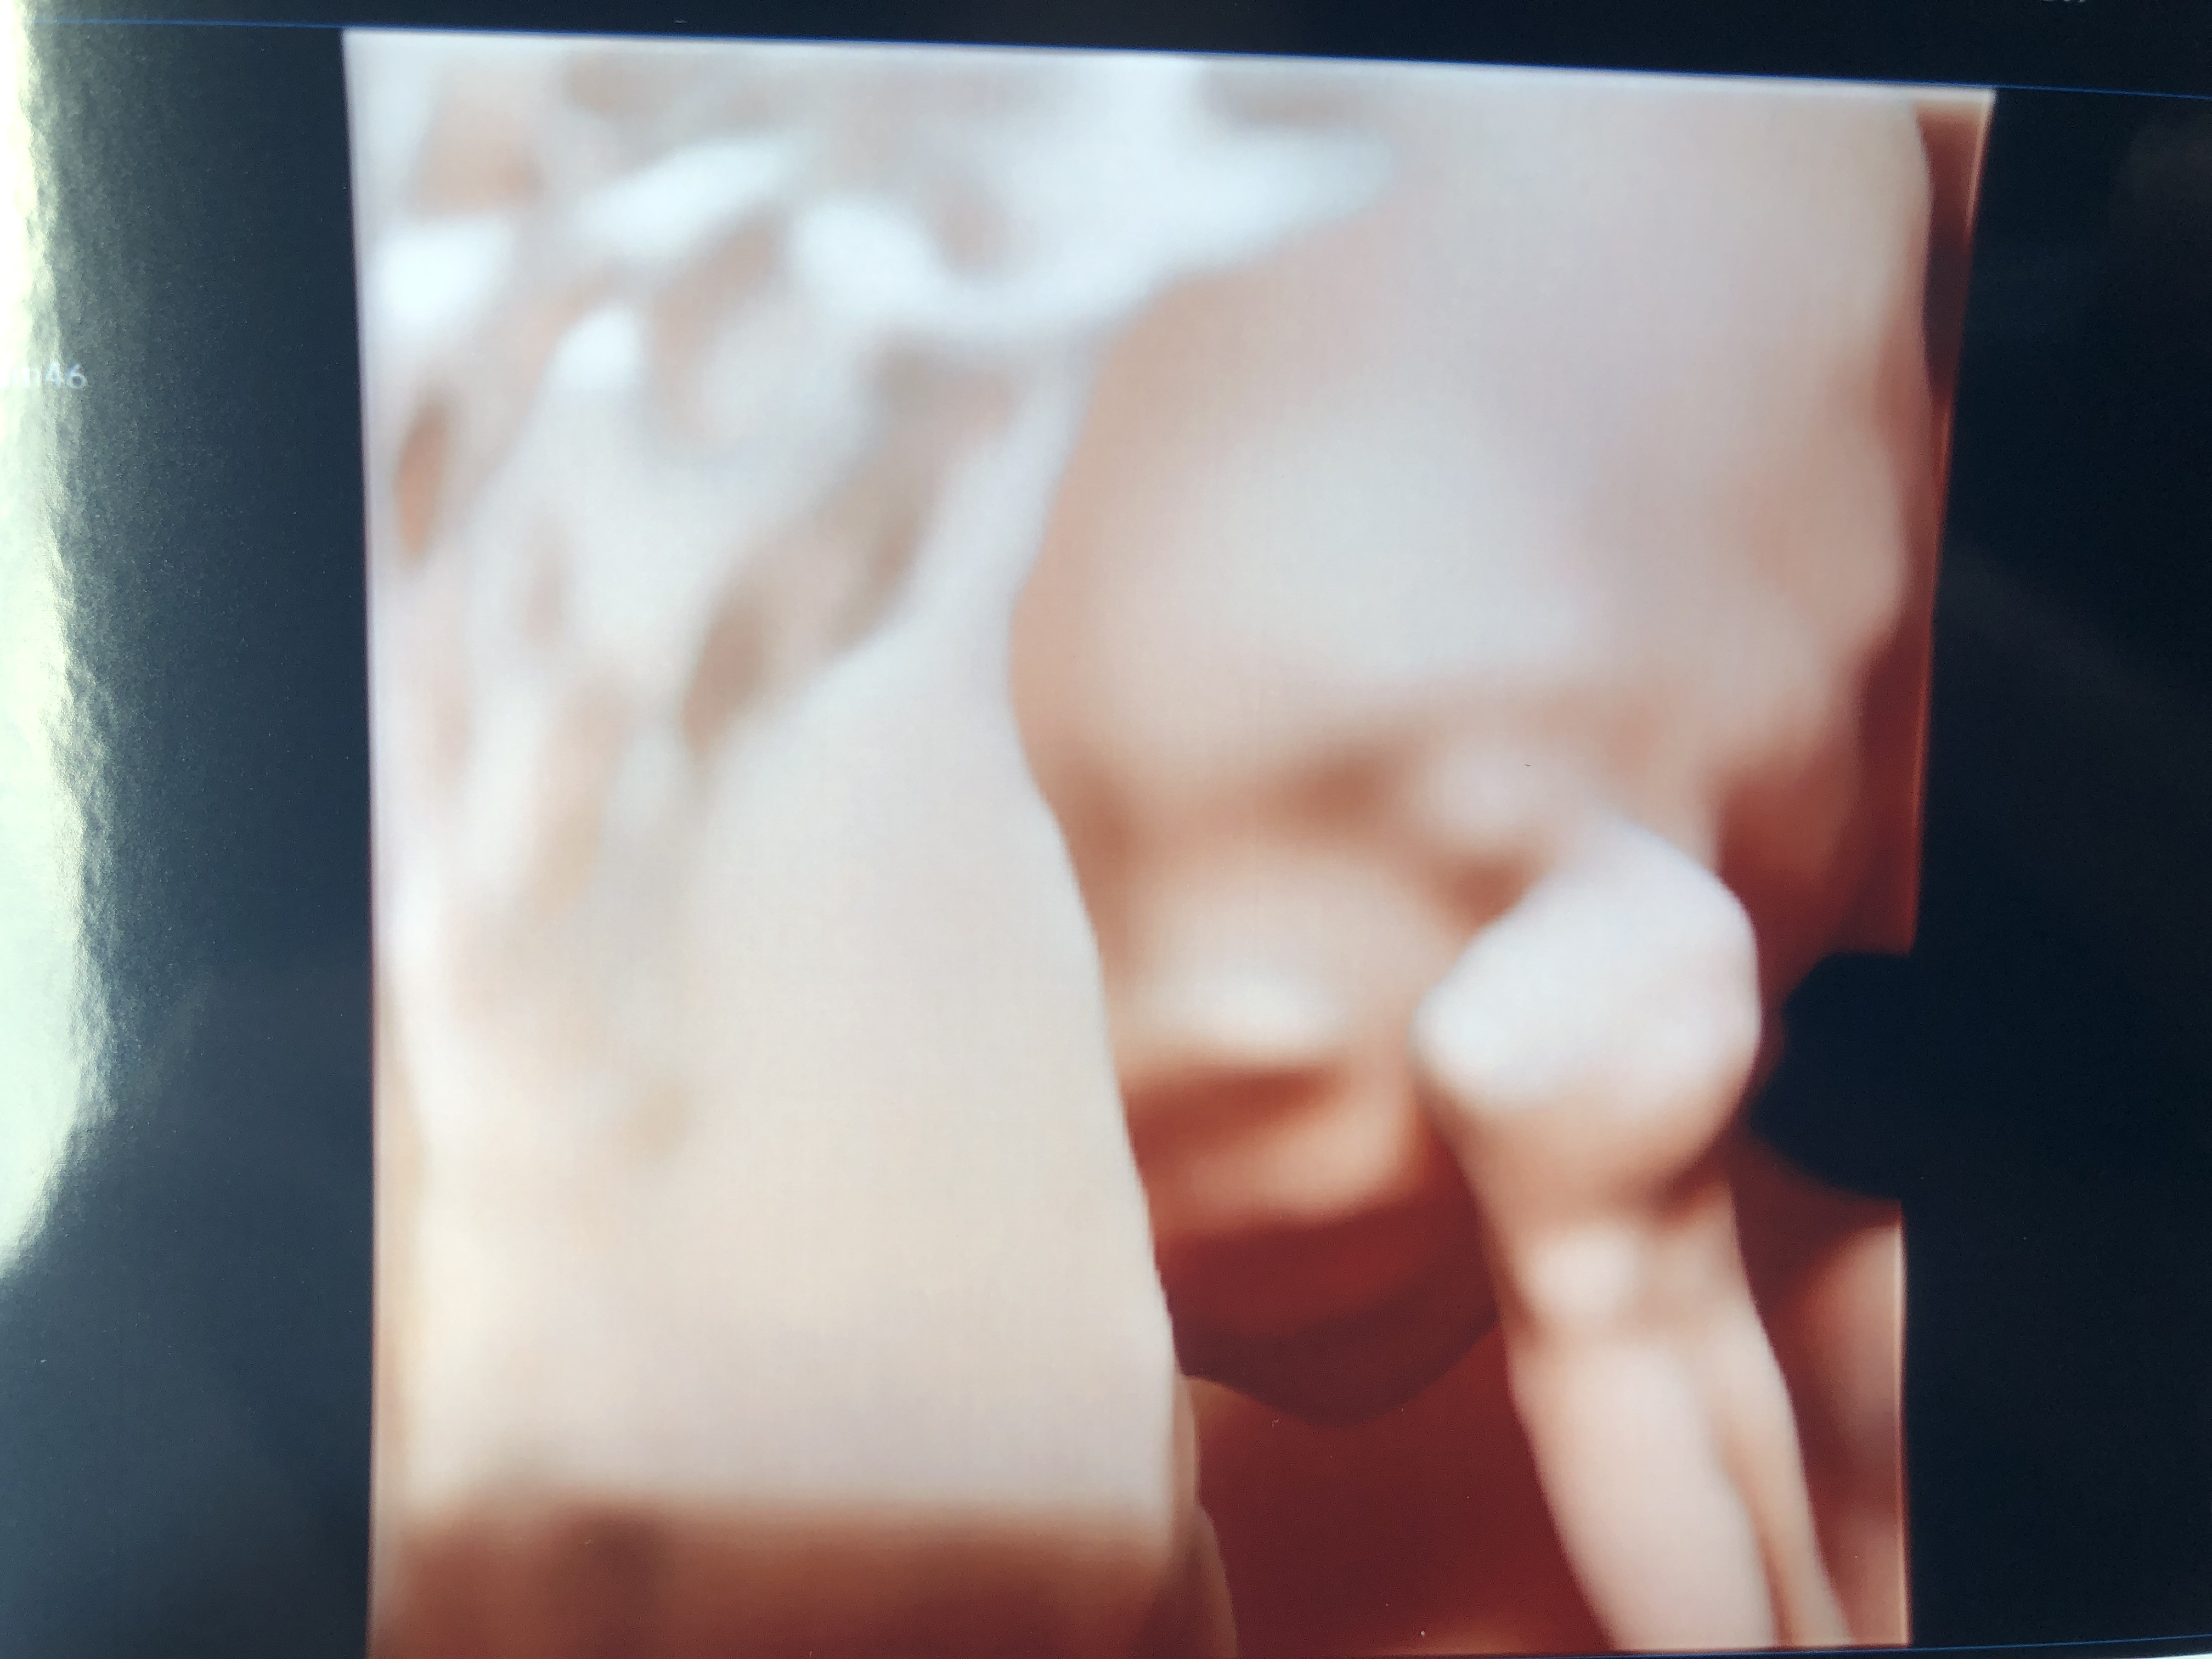

@Isanaa @AliG jednak mały falstart z tym mężem Bo ostatecznie nie mógł wejść. Zależy od lekarza a akurat pani dudzik tego nie robi. Miałam go cały czas na facetime i piękne zdjęcia zrobiłyśmy ale być to nie był. Córeczka zdrowa i bez najmniejszych podejrzeń o cokolwiek. Badanie tak dokładne ze paliczki w palcach policzone. Prawie 300 gr dzidziusia. Oby tak dalej :)

Załączniki

• EF2A4DC1-A65B-4CEF-A1AF-54FD1B0BBD54.jpeg

EF2A4DC1-A65B-4CEF-A1AF-54FD1B0BBD54.jpeg

1,3 MB · Wyświetleń: 144